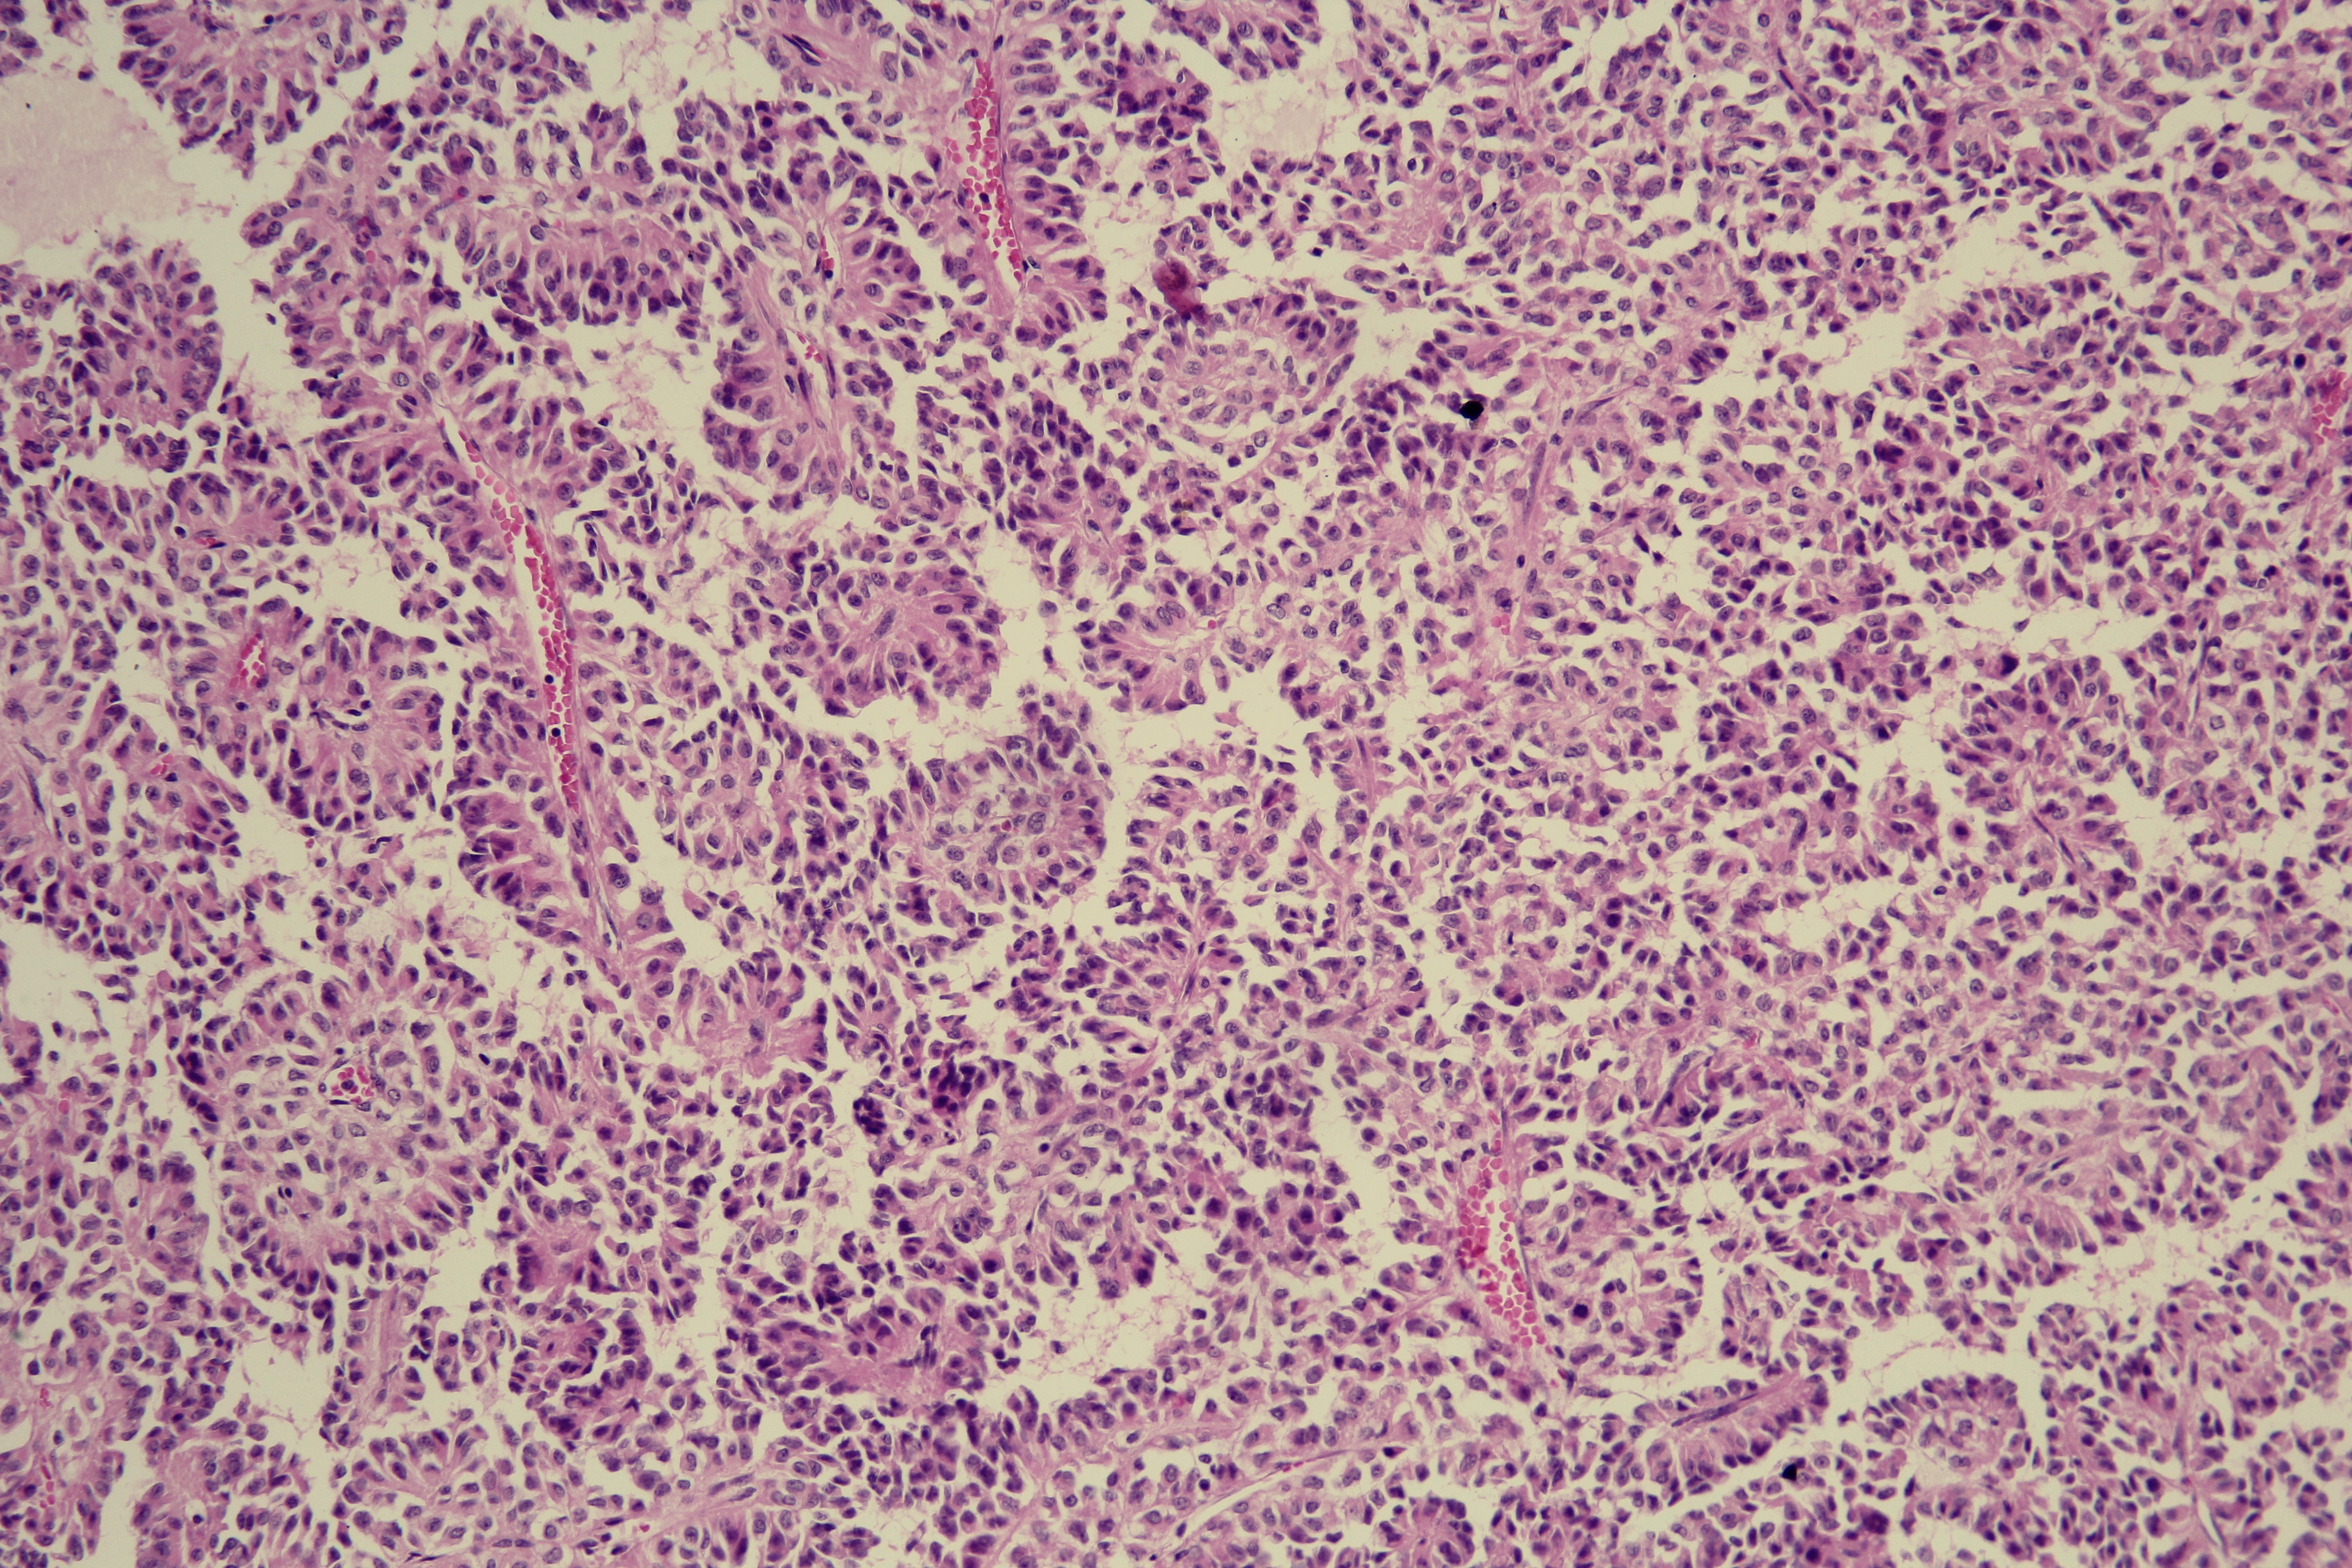

Results. Thirteen patients with SPT were identified (10 females), with a median age of 30 years. The main clinical presentation was abdominal pain (92.3%). The tumor was mostly located in the body or tail of the pancreas (77%), and the mean size was 8.2 cm. Regarding the surgical approach there were 5 distal pancreatectomies with splenectomy, 3 body and tail pancreatectomies, 2 body and tail pancreatectomies with splenectomy, 2 pancreato-duodenectomy, 1 partial enucleation and of all only 2 partial resections. Postoperative hematoxylin- eosin staining and immunohistochemistry confirmed the diagnosis in all cases. None of the patients had lymph nodes metastases. Only one local invasion. There was one case of death due to postoperative complications. Four cases followed adjuvant systemic chemotherapy. The mean follow-up was 18 months, without evidence of recurrence during this period.